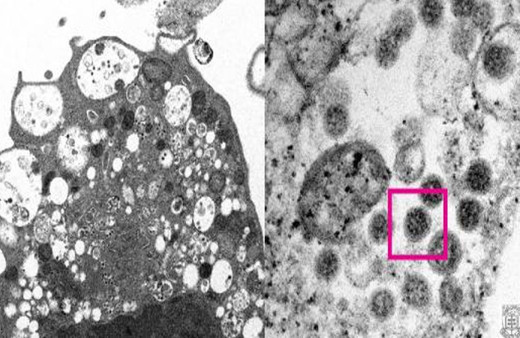

Omicron